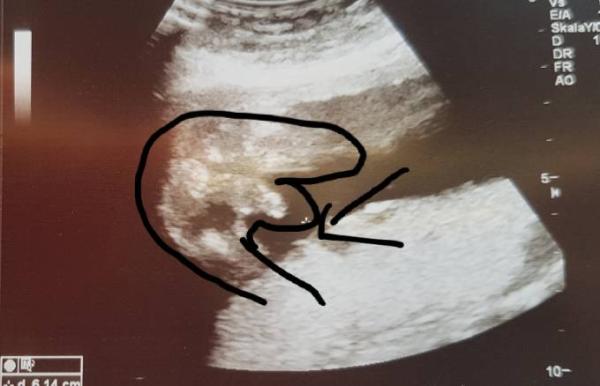

Ich hatte heute 2. Großes Ultraschall. Da ich schon ein Jungen habe, wollte ich unbedingt ein Mädchen. nun haben wir dieses Bild bekommen und die FA Ärztin sagte das es eindeutig ist. Besteht denn die Hoffnung das es vielleicht eine Nabelschnur sein könnte?

Sodas ich vielleicht doch noch auf ein Mädchen hoffen kann?

schaut aber aus wie ein zipfi

Das ist ganz eindeutig ein Junge. Ich habe selber 2 und kann dir sagen das ist wirklich mehr als eindeutig. Man erkennt ja sogar die Hoden.

Sehe da einen Hoden und Anhang.

Bei unseren großen Sohn sah es so aus. Ganz eindeutig

Aber ich denke euer Outing ist auch sehr sicher ein kleiner Junge.

Dem US Bild zu urteilen würde ich aber auch sagen, da fällt wohl nix mehr ab. Bei mir war es auch mehr wie eindeutig und da hat der Feindiagnostiker gleich gesagt, da ändert sich nix mehr.

oh das ist leider keine Nabelschnur ;-) das ist ein kleiner Junge..wie bei uns.